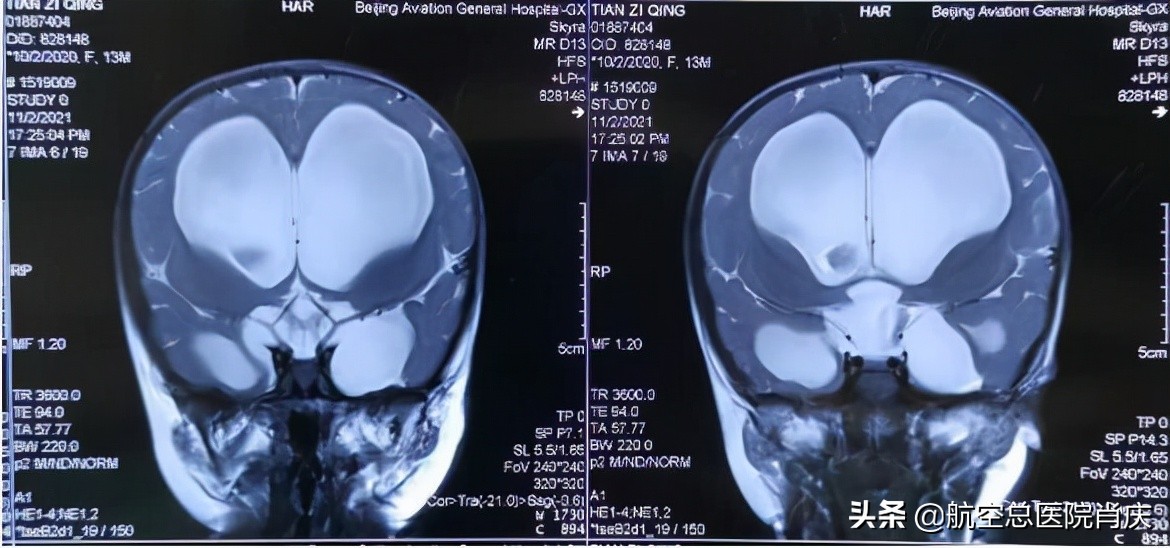

(术前冠状位片示脑室扩张,双侧颞极蛛网膜囊肿)